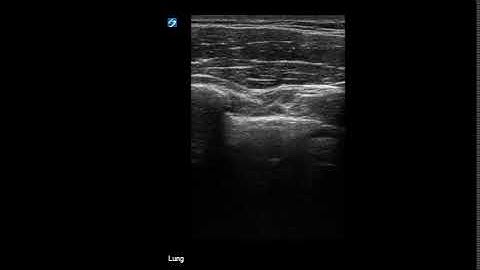

M Mode for Lung Ultrasound - Lung Sliding